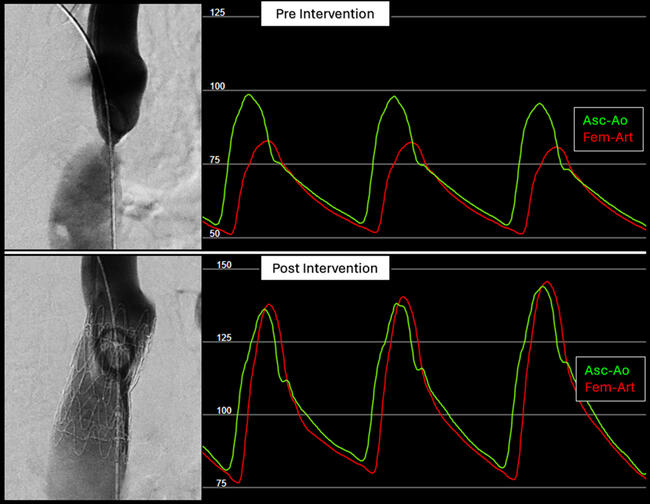

Self-Expanding Aortic Endografts for Endovascular Repair of Native and Recurrent Coarctation of the Aorta

Video Supplement to "Self-Expanding Aortic Endografts for Endovascular Repair of Native and Recurrent Coarctation of the Aorta" (Original Article).